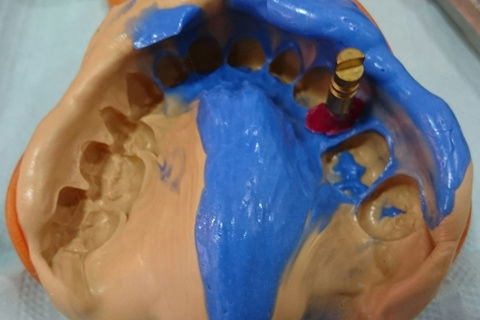

Personalização do transfer para moldeira fechada respeitando a coroa provisória.

Moldagem da coroa provisória para personalização do transfer.

Moldagem de trabalho.

Moldagem de trabalho com transfer personalizado.